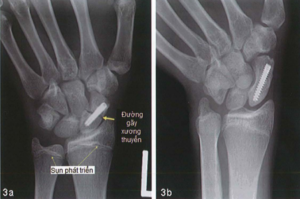

- Mổ nắn kín áp dụng với những trường hợp chấn thương mới, gãy ít di lệch:Trong trường hợp này có thể dùng kim Kirschner, vít nén ép rỗng lòng dưới màn tăng sáng. Phương pháp này mang lại hiệu quả tốt, ít tổn thương phần mềm